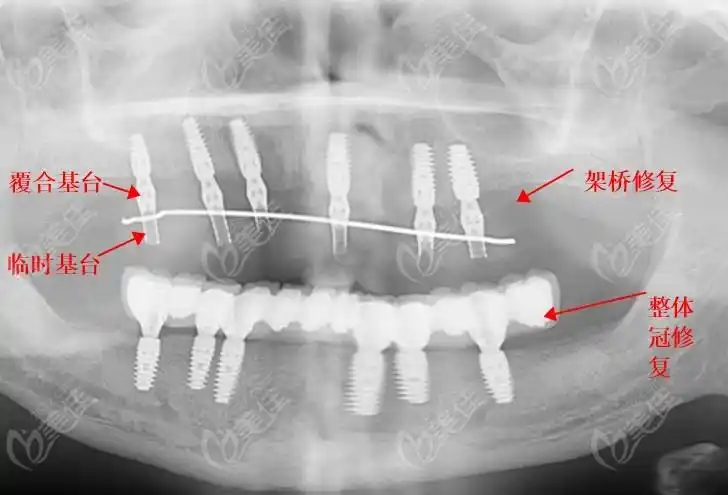

种植修复结构,你可以把它理解为一种桥架,是用搭桥的方式将缺失的牙齿

种植桥架(hpp)

种植纯钛桥架